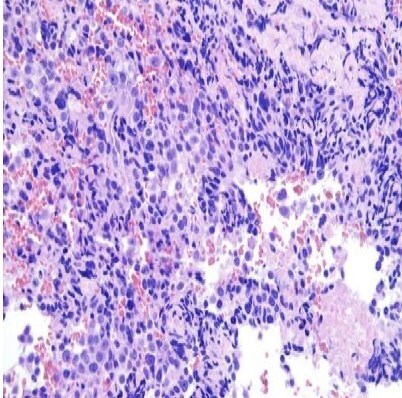

Anaplastic thyroid carcinoma (ATC) is a highly aggressive thyroid malignancy, comprising 1%-4% of thyroid cancers, with rapid local invasion and distant metastasis. We report a 57-year-old male with ATC presenting with a neck mass, hoarseness, and dysphagia. Imaging showed cancer thrombus in bilateral internal jugular veins, with a biopsy confirming ATC. This case highlights the imaging and pathological features of ATC and emphasizes the importance of ultrasound in evaluating intravascular cancer thrombus, aiding accurate diagnosis and management.

间变性甲状腺癌(ATC)是一种高度侵袭性的甲状腺恶性肿瘤,占甲状腺癌的1%-4%,具有快速的局部侵袭和远处转移。我们报告一位57岁男性ATC患者,表现为颈部肿块、声音嘶哑和吞咽困难。影像显示双侧颈内静脉癌栓,活检证实为ATC。本病例强调了ATC的影像学和病理特征,强调了超声在评估血管内癌血栓,帮助准确诊断和治疗中的重要性。